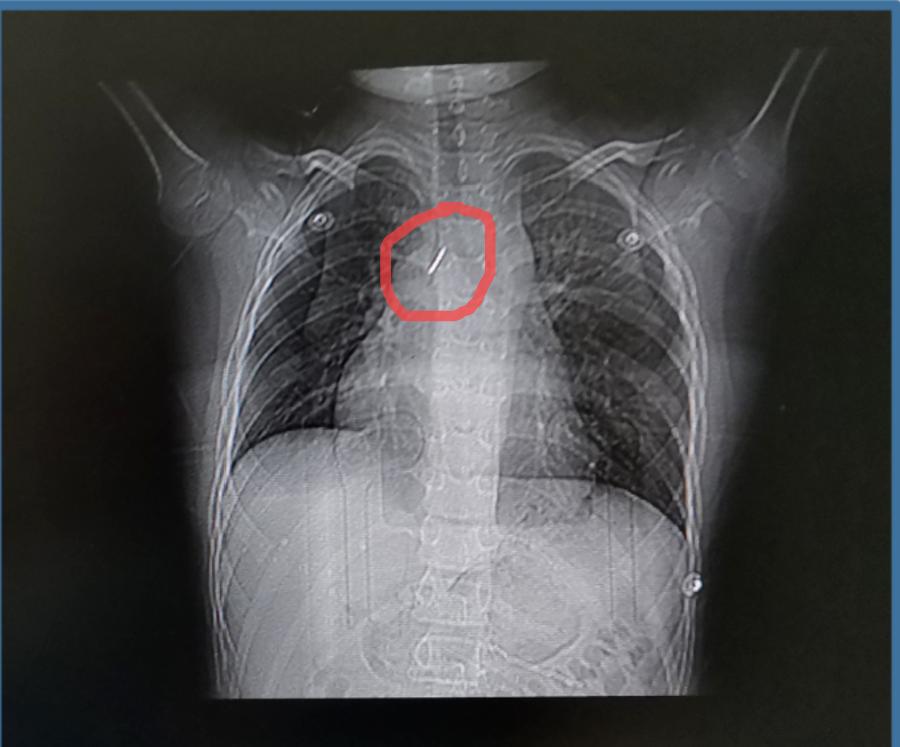

新乡一名9岁的男童牛牛(化名),在学校期间玩图钉,不慎吸入气管,出现胸闷及呼吸困难 ,当地医院行胸片及胸部CT证实异物在右主支气管,针尖朝上,有可能损伤气道,引起气管瘘等并发症,非常危险,后通过手术将图钉取出,保住了生命。